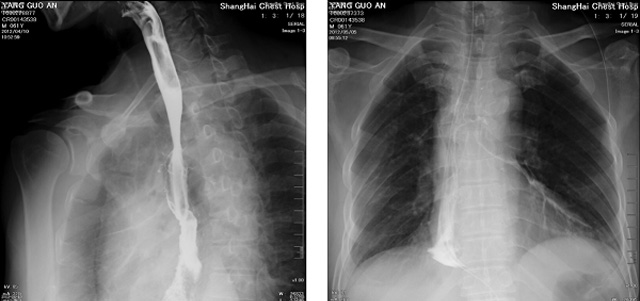

DR設(shè)備在2020年的新冠疫情中,加速了市場調(diào)整。以醫(yī)院為主的向二三級市場轉(zhuǎn)變。特別是小巧靈活的移動(dòng)DR設(shè)計(jì),填補(bǔ)CT和磁共振不能三維檢查的缺點(diǎn),滿足內(nèi)科外科特別是骨科的影像診斷需求。還有懸吊DR設(shè)備CT斷層射線系統(tǒng)。使用錐束成像技術(shù)對整個(gè)脊柱和整個(gè)下肢進(jìn)行了體積三維掃描。無需使用對比劑,即可使用X射線呼吸功能標(biāo)測來模擬模擬氣流和血流,以評估患者的肺動(dòng)脈血栓。